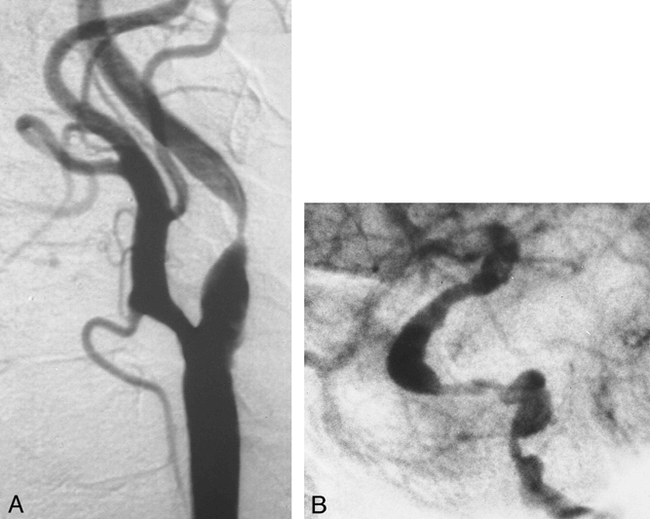

69-year-old woman with left hemispheric TIAs and left orbital bruit.

A and B, Cerebral angiograms show an 80% left ICA stenosis (A) and an 80% left carotid siphon stenosis (B). This is the only patient in whom the chart review indicated that the presence of tandem stenoses was the reason an endarterectomy was not performed.